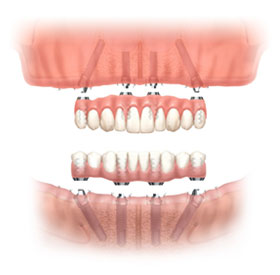

All-on-Fou/Six

近年來由於人工植牙的技術普及,患者大都知道植牙可做固定式假牙,但同樣的有時患者因為身體、經劑因素等受限,也可以考慮植入幾支人工植牙,再完成固定可撤式活動義齒,這樣可讓活動式假牙的固定性有效加強。通常上顎可用6支植體,下顎則4-5支植體固定,如需更穩定的受力,亦可再增加植體數目。(圖52-55)

圖52

圖53

圖54

圖55